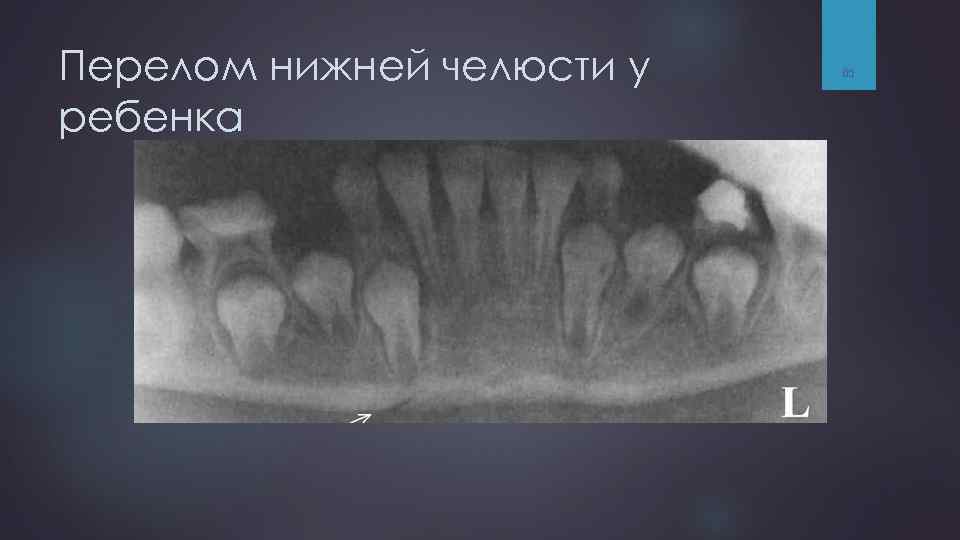

Особенности переломов нижней челюсти у детей связано с особенностями строения детских костей и их физиологическими свойствами. Нижняя челюсть у детей тоньше и менее прочна, т. к. менее минерализована, чем взрослых. Надкостница толстая, обильно пронизана сосудами, поэтому у детей часто встречаются переломы по типу “зеленой ветки” или “ивового прута”. Другой характерной особенностью переломов нижней челюсти в детском возрасте является травматический остеолиз. 63

Oсобенности переломов нижней челюсти у детей Остеолиз встречается при переломах шейки мыщелкового отростка нижней челюсти и характеризуется полным рассасыванием костного вещества головки. Через 2 -3 месяца после травмы исчезновение головки выявляется рентгенологически, а в более поздние сроки формируется ложный сустав (неоартроз). При этом движение нижней челюсти сохраняется в полном объеме. Но возможно обнаружение отставания в росте нижней челюсти на стороне перелома. В детском возрасте около 30% повреждений нижнечелюстной кости сопровождается переломом суставного отростка. что в 3 -9 летнем возрасте шейка суставного отростка является наиболее слабым местом при физическом воздействии. 64

Перелом нижней челюсти у ребенка 65